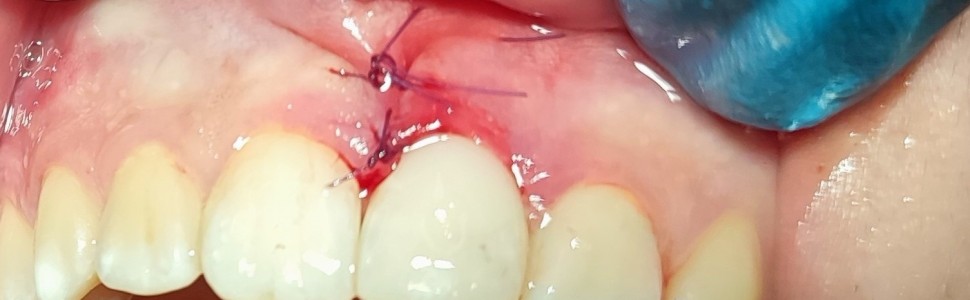

Przyszyjkowa resorpcja zewnętrzna najczęściej dotyczy górnych zębów siecznych przyśrodkowych. Metoda leczenia oraz rokowanie zależą w dużej mierze od rozległości ubytku oraz możliwości uzyskania dostępu do jamy resorpcyjnej. W artykule szczegółowo opisano metodę chirurgiczno-zachowawczą, którą zastosowano (w połączeniu z leczeniem endodontycznym) u 15-letniego pacjenta w przypadku pourazowej przyszyjkowej resorpcji zewnętrznej w zębie siecznym górnym przyśrodkowym lewym. W pracy przedstawiono także wyniki 22-miesięcznej obserwacji.

Cervical internal resorption most commonly affects the maxillary central incisors. The treatment method and prognosis largely depend on the extent of the defect and the possibility of accessing the resorptive cavity. This article provides a detailed description of a surgical-conservative approach combined with endodontic treatment, along with a 22-month follow-up on the effectiveness of the applied procedure.